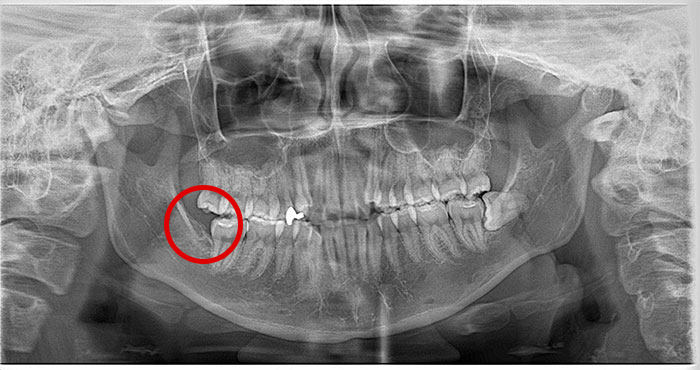

親知らずの症例

Before

After